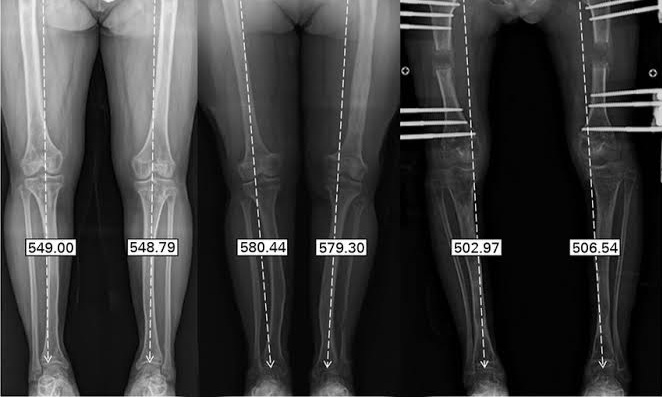

نجاح معجزة طبية: طفل ينجو بعد انفصال رأسه عن عموده الفقري

حقق الطبيب اللبناني الأمريكي محمد بيضون إنجازًا طبيًا وصف بأنه "سابقة علمية" و"معجزة طبية"، بعدما نجح في إجراء عملية جراحية معقدة لطفل ألماني يبلغ من العمر عامين. كان الطفل أوليفر تورين قد تعرض لحادث ...